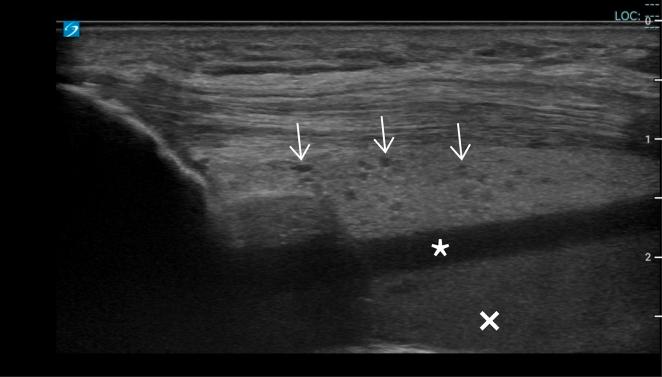

Woman With Left Knee Pain.

Ultrasound for knee effusion: lipohaemarthrosis and tibial plateau fracture.